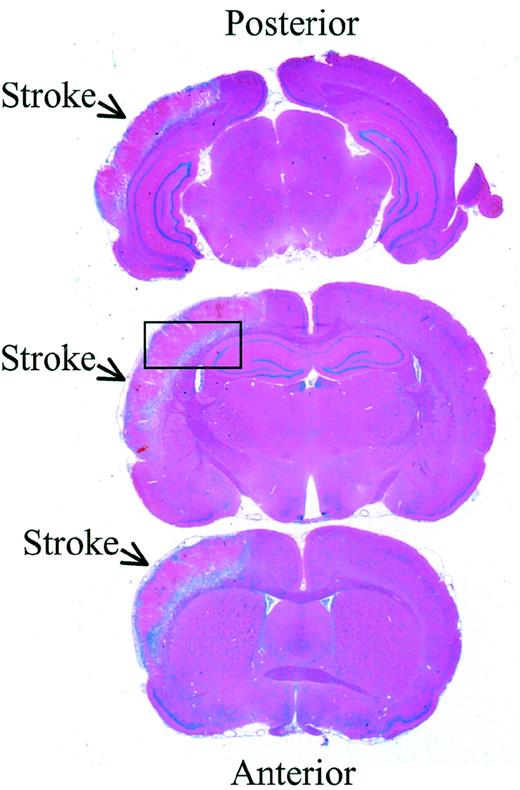

Rats were anesthetized with pentobarbital intraperitoneally 72 hours after infarction and brains were removed after transcardiac perfusion with PBS and paraformaldehyde 4% (Fisher Scientific, HC-200). The entire brain was embedded in paraffin and coronal sections, 20 μm thick, were cut through the rostrocaudal extent of the brain (Figure1). The sections were stained with hematoxylin-eosin and using the NIH Image Analyzer System, the total volume of each infarction was determined by the integration of the areas of 8 chosen sections and the distances between them. The rostral and caudal limits for the integration were set at the frontal and occipital poles of the cortex.39 Statistical significance between groups of animals was identified by a Student t test.

Rat brain sections 72 hours after reperfusion

. Hematoxylin-eosin stain of 3 representative sections from the same brain 72 hours after reperfusion. The infarcted area is indicated with arrows, and the box indicates the location where higher resolution analysis was performed (magnification × 5).

Because tPA may contribute to neuronal death after cerebral infarction, increased expression of neuroserpin might play an important role in neuronal survival after stroke. To examine the expression of neuroserpin after cerebral ischemia, immunohistochemical staining of brain sections was performed at 6, 24, 48, 72, 96, and 168 hours after MCA occlusion and reperfusion. Figure 1 shows 3 representative brain sections harvested 72 hours after reperfusion and stained with hematoxylin-eosin. The infarct is clearly evident as the lighter stained tissue in the cortex of the left hemisphere, and the box indicates the area where higher resolution analysis was performed. Neuroserpin immunoreactivity was increased in the area surrounding the ischemic core (penumbra) and in the ipsilateral hippocampus as early as 6 hours after stroke and remained elevated up to 168 hours when compared with the contralateral, nonischemic hemisphere or with sham-operated controls (data not shown). The peak of neuroserpin immunoreactivity in both the number of neuroserpin-positive cells and in the intensity of the staining appeared to be at 48 hours following reperfusion (Figure 2). The apparent rapid increase in neuroserpin expression following infarction suggests that the surrounding surviving cells may be up-regulating neuroserpin expression in response to the ischemic insult.